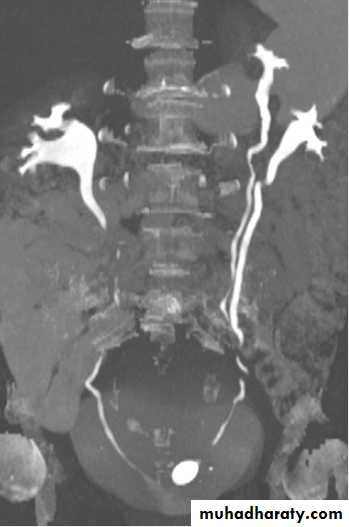

CT scanContrast enhanced CT scan through the kidneys in nephrogram phase 90-100 seconds following contrast administration and would show renal lesions well.

Contrast enhanced CT scan through the kidneys in pyelogram phase (showing excretion of contrast into the collecting system). This is approximately 10-15 minutes following contrast administration and would show urothelial lesions well, such as transitional cell carcinoma, stones, blood clots.